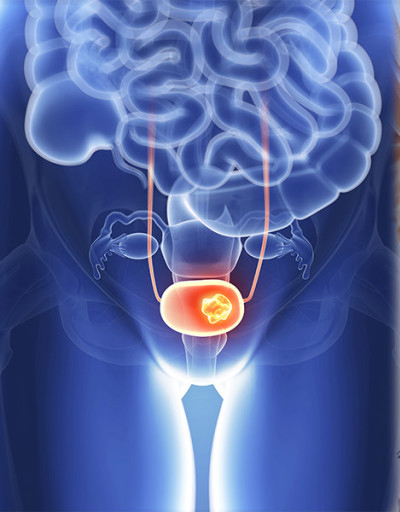

전립선은 방광 바로 아래에 위치하며 요도를 감싸고 있기 때문에, 전립선에 암이 발생하면 주로 소변(배뇨)과 관련된 증상들이 초기부터 나타나는 경우가 많습니다. 다음은 전립선암 환자들이 흔히 겪는 10가지 주요 초기 증상입니다.

- 허리, 엉덩이, 다리 통증

- 설명: 전립선암은 뼈로 전이가 잘 되는 암입니다. 암세포가 척추, 골반, 허벅지 뼈 등으로 전이되었을 경우, 해당 부위에 지속적이고 심한 통증을 유발합니다. 이는 암이 상당히 진행된 경우에 나타나는 증상입니다.